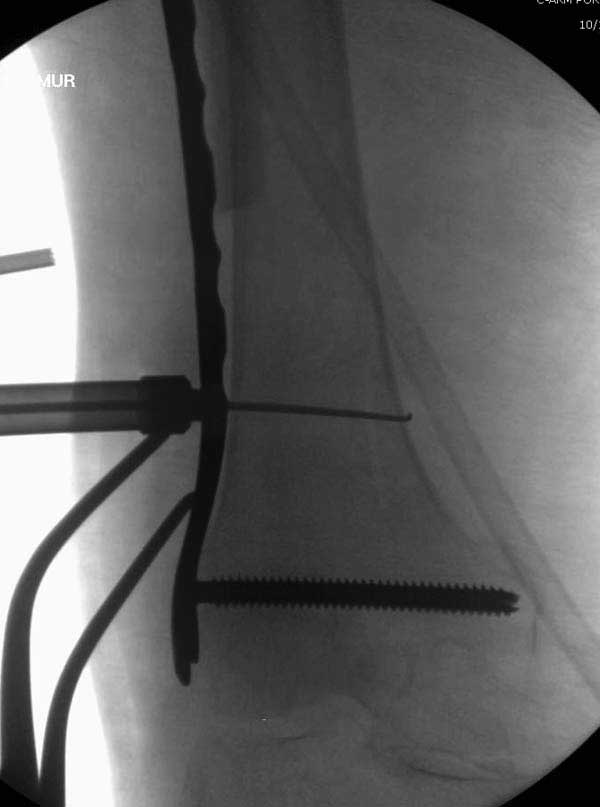

Такие “чужие осложнения” встречаются у всех и представляю банальный случай, который шаг за шагом показано как перерос в более сложный процесс... Больная 70 лет, множественные ко-морбидности, чрезвертельный перелом первоначально фиксирован Гамма 3. Осложнение в течение 6 недель, ревизия тотальной артропластикой и во время установки ножки обнаружена трещина диафиза (17), из малого доступа фиксация алло-графтом.

Повторно поступает после двух с половиной лет, где обнаруживается перелом на второй стороне. Немного сложно, но для фиксации выбрали Antegrade InterTan Smith Nephew Nail и с момента фиксации более 3х мес.